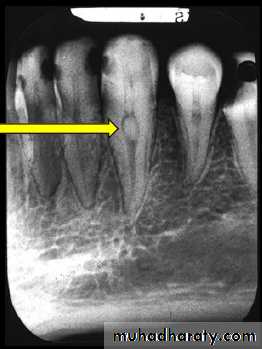

- Size of the lesion:

Pulp pathosis→periapical lesion(abcess →granuloma →cyst)

(The smaller the radiographic emage, the more likely the diagnosis is granuloma is correct)

According to Lalonde:

0-1cm →70% granuloma-30% cyst.

1-2cm →40% granuloma-60% cyst.

↑2cm →100% cyst.

Tay etal demonstrated that the success of conservative endodontic therapy deminished with the increased size of the periapical lesion